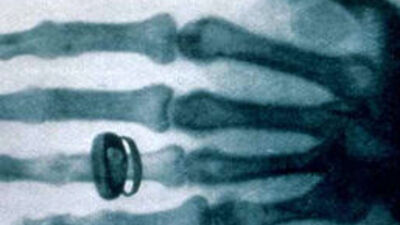

Der Physiker Wilhelm Conrad Röntgen (1845-1923) beschäftigt sich in Würzburg mit Kathodenstrahlen. An den Elektroden einer ummantelten Vakuumröhre entlädt sich elektrische Spannung, die Röntgen im Dunkeln genauer untersucht. Dabei leuchtet ein zufällig auf einem Labortisch liegendes Plättchen, das mit einer chemischen Substanz bestrichen ist – die Strahlung kann, anders als Licht, die Ummantelung mühelos durchdringen. Seine Entdeckung revolutioniert die medizinische Diagnostik: Nun sind Bilder vom Inneren des Körpers möglich - wie hier von der Hand des Anatomen Albert von Koellikers, aufgenommen von Conrad Röntgen am 23. Januar 1896.